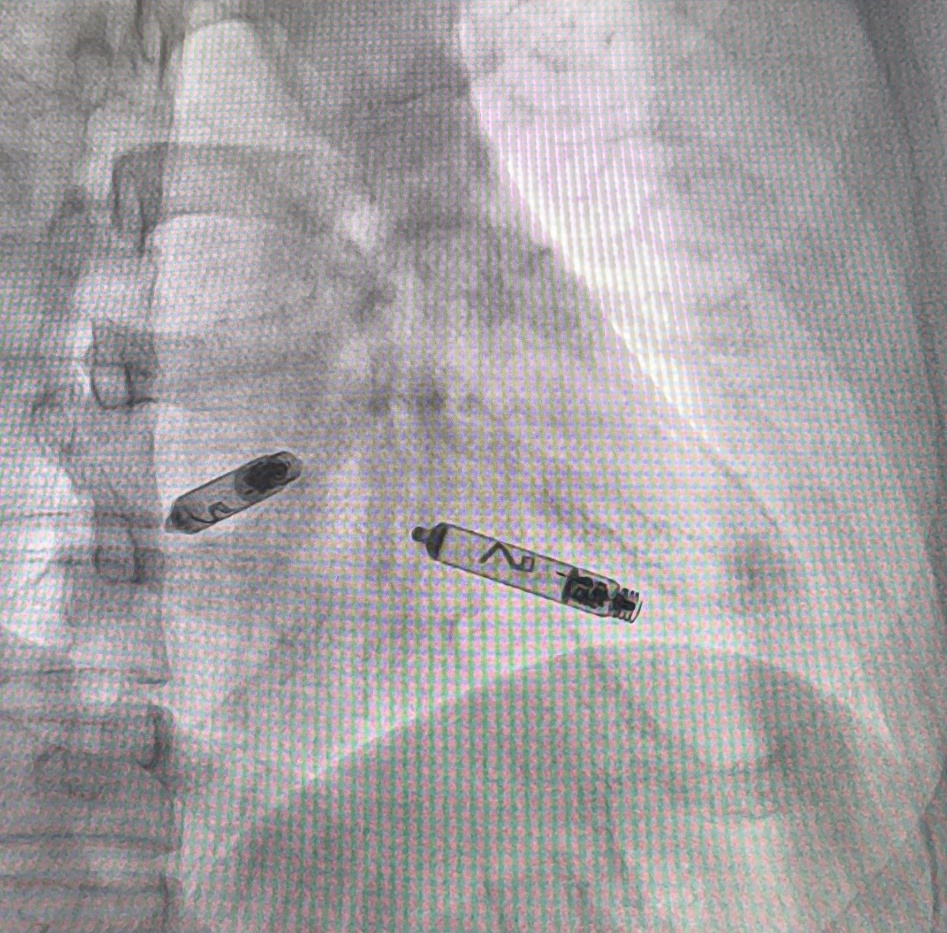

本次手术患者为56岁中年女性,入院诊断为“间歇性三度房室传导阻滞、二度II型房室传导阻滞”,根据病情,吉林大学中日联谊医院心内科贺玉泉主任团队经全面评估后,认为无导线DR起搏器的微创特性与双腔同步起搏功能,能最大程度保障治疗安全性与有效性,满足患者高质量的生活需求;手术中,团队凭借丰富的介入治疗经验,在40分钟内,通过精准定位与先进的i2i通信技术,实现两枚脉冲发生器的"隔空协同",成功完成右心房与右心室的双腔起搏部署,术中参数测试满意,术后右腿股静脉穿刺处加压包扎8小时候即可下床恢复正常活动。

雅培AVEIR™ DR植入式无导线心脏起搏器是全球首个且目前唯一一款真正在右心房和右心室分别植入设备的双腔无导线起搏系统。与传统双腔起搏器相比,双腔无导线起搏器无需在胸前制作囊袋和植入电极导线,这使其在避免导线或囊袋相关并发症、消除体表疤痕、保留血管通路方面优势显著,同时能实现生理性的房室顺序起搏,创伤更小,恢复更快。该技术作为全球领先的无导线起搏解决方案,对医生的操作精准度和术前评估能力提出了更高要求。此次首例植入的成功,体现了团队对新技术的快速掌握与高效落地,也拓展了省内心律失常治疗的适应症范围,尤其为血管条件差、对生活质量有较高要求的患者提供了全新治疗方案,更推动吉林地区心脏起搏治疗水平向国际化、微创化、精准化迈进,为区域心血管健康保障体系建设注入强劲动力。吉林省中日联谊医院将继续以患者为中心,推动高质量医疗服务不断升级。